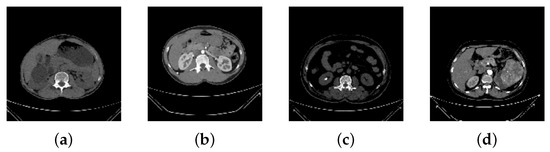

The coronal and axial cuts were selected from both contrast and non-contrast studies to create DICOM images of the ROI for each radiological finding. For better computational efficiency, pixels were re-scaled into the [0, 1] range, and each image was resized to 150 × 150 pixels.In order to maintain a percentage of samples for each class, stratified sampling was utilized the training-and-testing split results. Figure 1 shows the sample images for individual categories.

Figure 1.

Sample Images from the Dataset. (a) Cyst, (b) Normal, (c) Stone, (d) Tumor.